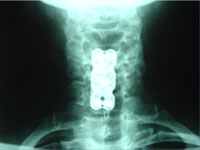

- Case Report: Cervical Spine Post-Surgery

Probably no area of chiropractic spinal manipulation is as challenged as treating the post-surgical patient who is the same, worse, or disenchanted with their surgical outcome. Certainly, the opportunity to treat the patient before surgical intervention is best. When confronted with this post-surgical patient, however, the chiropractic physician proceeds as if with a patient who has not had surgery. i.e. The chiropractor will proceed with the careful history and clinical examination to determine what is causing the pain. That cause may be within the surgical site or adjacent to it. In treating the post-surgical spine, fusion or no fusion is a dictator of care. If there is a fusion, spinal manipulation is given to adjacent levels of the spine to the fused area. If there is no fusion, the doctor carefully proceeds as if no surgery. Some motion may be possible within the spine depending on the surgical procedure performed. (11)